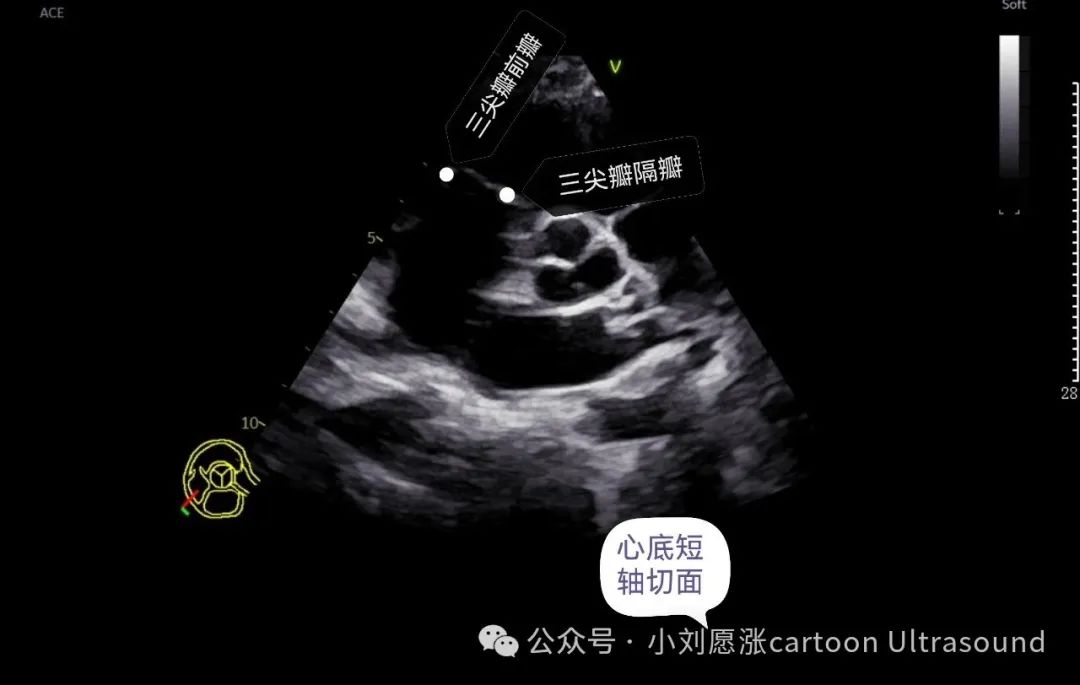

三尖瓣:3个瓣叶,前瓣、后瓣、隔瓣,后瓣只能右室流入道切面观察。

主动脉瓣:3个瓣叶,右冠瓣、左冠瓣、无冠瓣, 心底短暂切面 注意观察瓣叶个数,二叶是主动脉瓣畸形最多见。